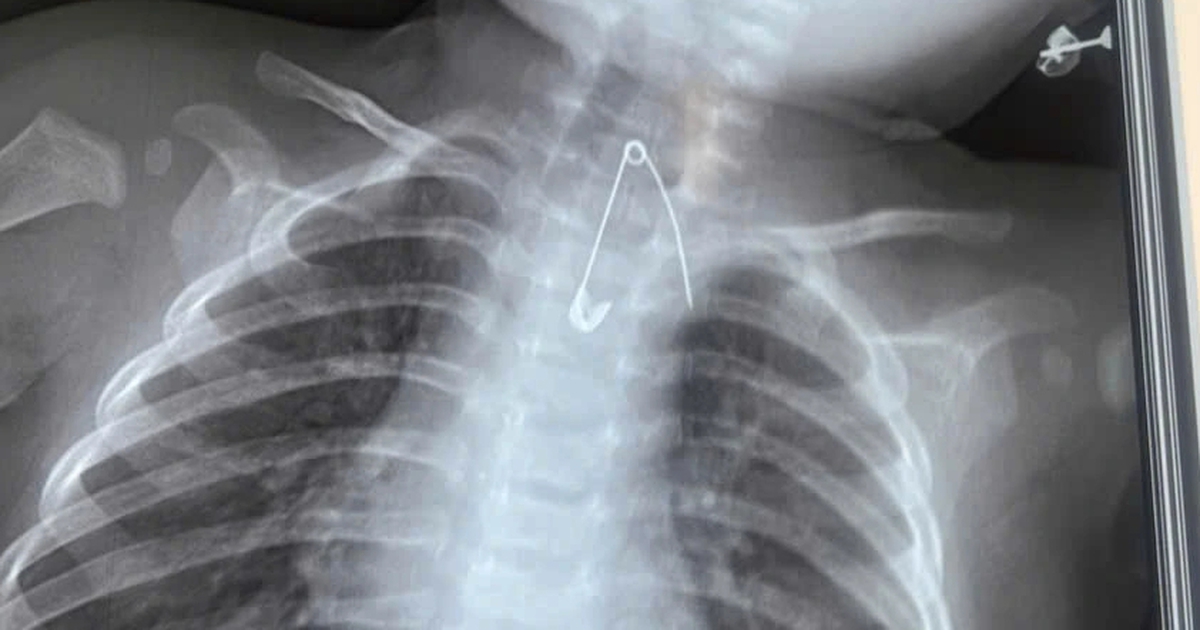

2 trẻ nguy kịch vì nuốt dị vật

Chỉ trong một thời gian ngắn, Bệnh viện Sản - Nhi Cà Mau đã tiếp nhận 2 bệnh nhi nuốt dị vật cực kỳ nguy hiểm.